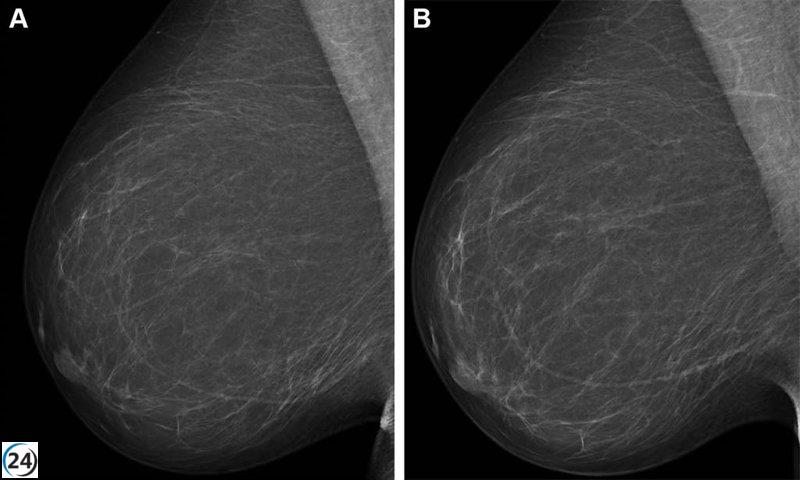

El Consejo de Gobierno ha aprobado un ambicioso proyecto que invertirá 1.597.200 euros en la implementación de un software de asistencia para el diagnóstico clínico, el cual se especializa en el análisis de mamografías mediante avanzados algoritmos de inteligencia artificial.

Esta inversión permitirá a los centros de Sacyl disponer de un sistema que apoyará la interpretación de mamografías, aliviando la carga de trabajo que supone la lectura manual de un gran volumen de pruebas. La Junta ha anunciado que la puesta en marcha está programada para dentro de cinco meses.

Con esta iniciativa, se busca agilizar los procesos de lectura y interpretación, ayudar en la identificación temprana de anomalías, priorizar los casos que requieran revisión y descartar con mayor precisión las mamografías que no presentan problemas. Todo esto contribuirá a mejorar la efectividad del programa de detección del cáncer de mama.